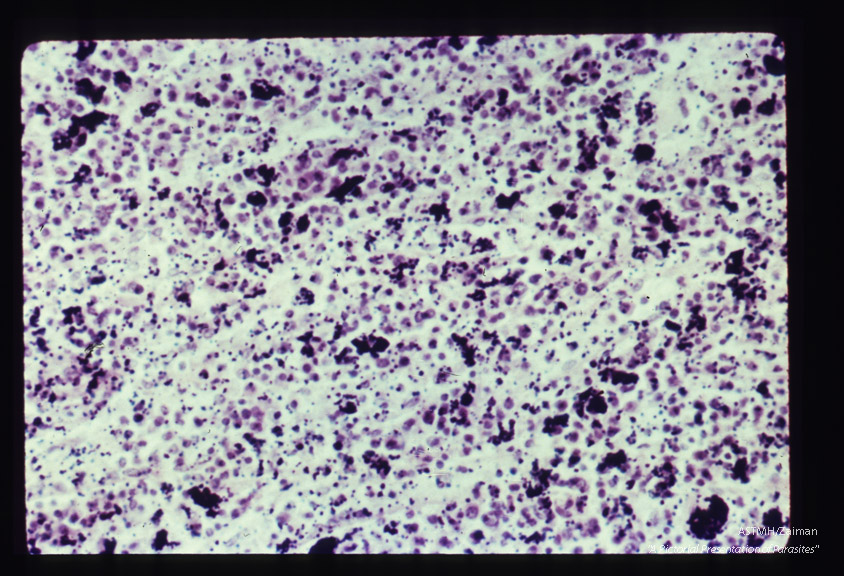

Pigment in human spleen.

Plasmodium falciparum

Description: Pigment in human spleen.